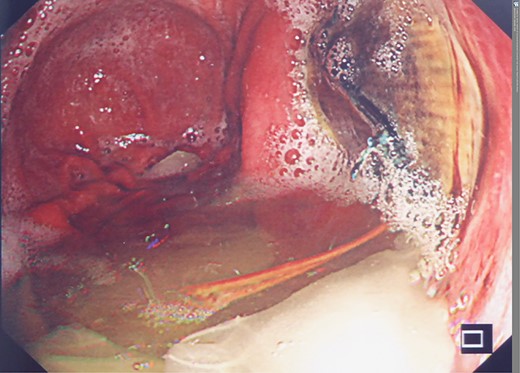

A week later, he underwent a further OGD. This showed a benign ulcer (Fig. 4), which was later confirmed histologically. Helicobacter pyloriwas negative. He was discharged home 8 days post stent insertion with a further 2-week course of co-amoxiclav (Amoxicillin/clavulanic acid) and 1 week of fluconazole, as recommended by a consultant microbiologist, and life-long omeprazole. He remained well for the next months.

However, 4 and a half months later he again became haemodynamically unstable with a further episode of haematemesis. A further CT angiogram showed contrast entering the neo-oesophagus from the thoracic aorta (Fig. 5). The patient was again taken to the emergency theatre and the previous stent was relined with further stents extending both proximally and distally beyond the previous stent, with care taken not to occlude the celiac trunk and arteries below this (Cook Medical ZTA-26-105 and Cook Medical ZTA-28-109). Again, the patient had a quick recovery. However, repeat endoscopy showed that the aortic stent was visible through a defect in the wall of the neo-oesophagus (Fig. 6).

Second admission: OGD post second stent insertion demonstrating visibility of aortic stent via defect in wall of neo-oesphagus.